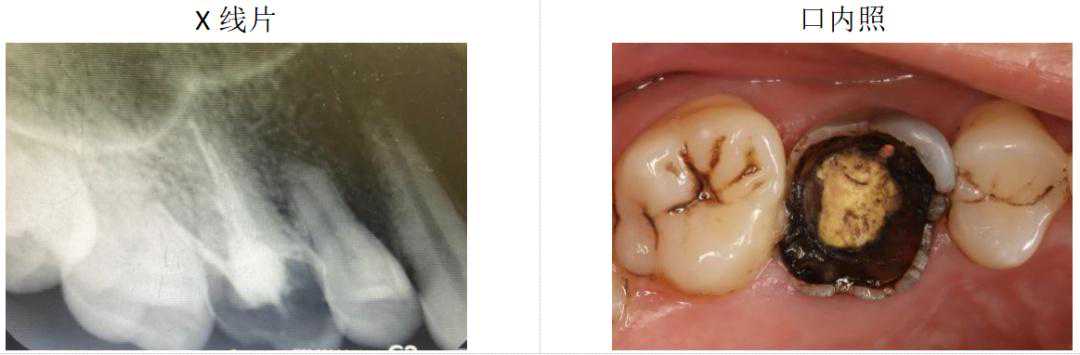

在临床工作中,牙齿残根带来的问题非常常见。残根是指牙齿的牙冠部已经全部缺失,只剩下牙根的部分。牙齿残根产生主要有两种原因,一是龋齿,也就是人们常说的蛀牙,二是外伤,牙冠被折断,只剩下埋在骨头里的牙齿根部。牙齿残根可能引发多种问题,需要及时治疗。

图2残根临床照片